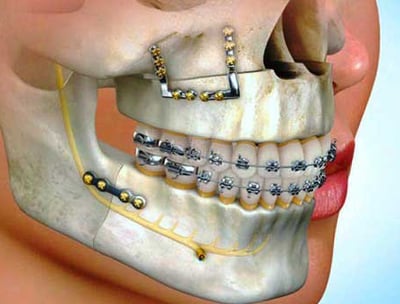

Oral and Maxillofacial Surgery

This specialty includes the diagnosis and surgical treatment of diseases, injuries, and defects of the mouth, jaws, and face, such as tooth extractions and corrective jaw surgeries.